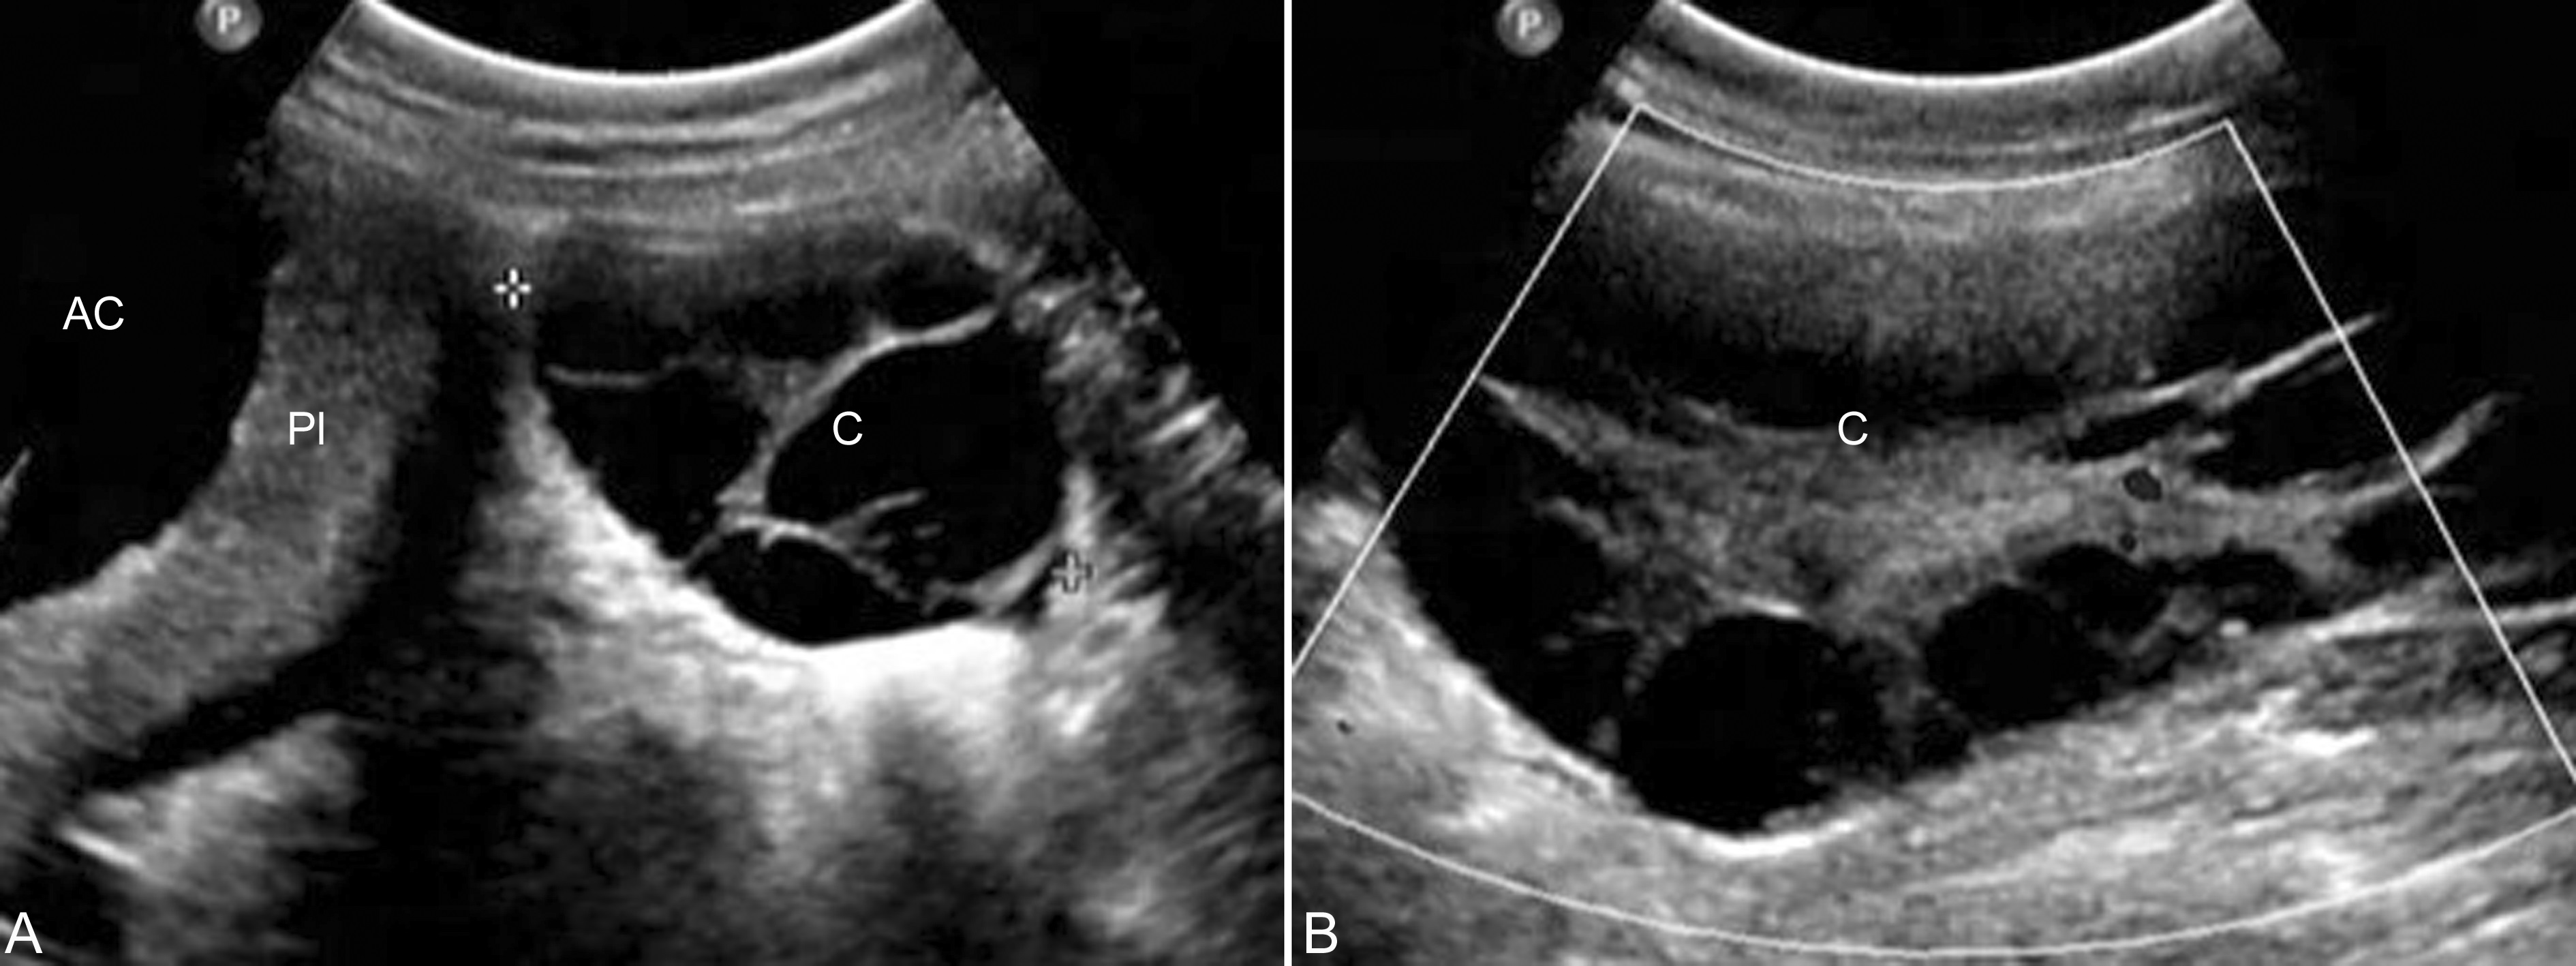

妊娠期卵巢浆液性囊腺瘤(serous cystadenoma of ovary)和粘液性囊腺瘤(mucinous cystadenoma of ovary)的发生率占附件区占位性病变的27.5%;超声显像检查其内部回声也与非妊娠期一样,均显示为典型的无回声区,形态规则,边缘清晰,壁比较薄。一般情况下,粘液性囊腺瘤多为单侧,瘤体较大,张力较低,显示为椭圆形或扁圆形,内部如有分隔则多为多发性,相对稍厚,无回声区内可见较低的分布均匀的回声(图3);浆液性囊腺瘤多数张力较高,显示为椭圆形或圆形,内部透声较好,有时可见分隔,但分隔多较少、较薄(图4),有15%的浆液性囊腺瘤为双侧。

图3妊娠并粘液性囊腺瘤声像图

羊膜腔(AC)外侧显示低张力、多房性无回声(C),内部可见不均匀分布的低回声

Pl:胎盘

图4妊娠并浆液性囊腺瘤声像图

子宫内显示孕囊回声(箭头处),子宫旁可见单房性囊肿,64mm × 58mm × 70mm